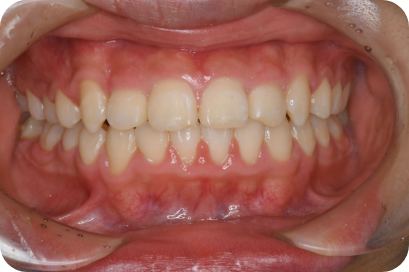

Nさん

Before

After

- 形態:

- 機能:

第2期治療

身体や顎の成長が終わり永久歯に交換してから全体の歯ならびと咬み合わせを整えます。

第一期治療を施していればほとんどが簡単な治療で終わることができます。

第二期からの治療(いわゆる大人の矯正)も行っています。